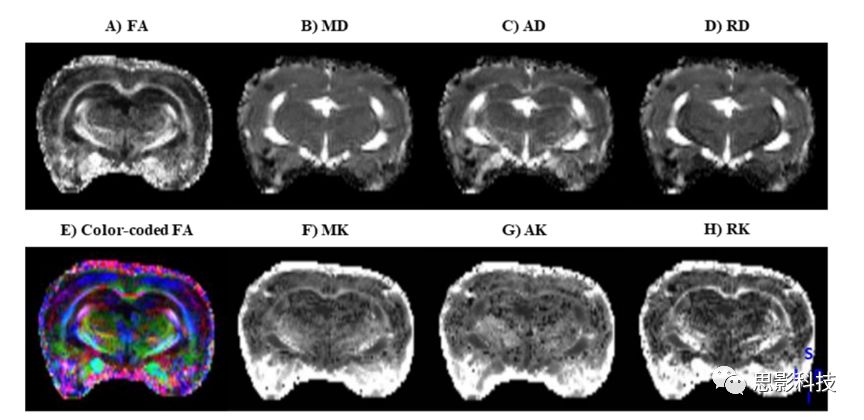

思影根據(jù)不同的數(shù)據(jù)類型以及客戶的不同需求,可構(gòu)建多種彌散模型(如彌散張量DTI、彌散峰度成像DKI、神經(jīng)突強(qiáng)度和散度成像NODDI等等)并計(jì)算對應(yīng)的彌散指標(biāo)。

DTI和DKI指標(biāo)圖圖例